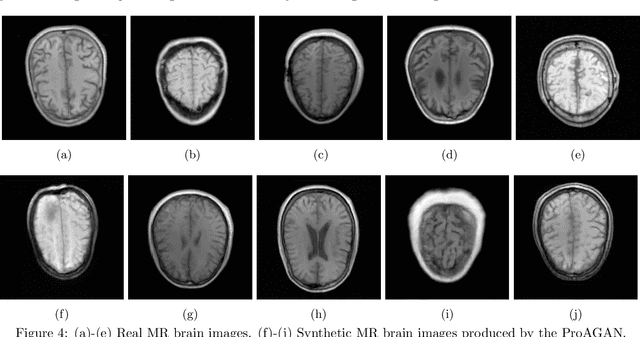

The objective optimization of medical imaging systems requires full characterization of all sources of randomness in the measured data, which includes the variability within the ensemble of objects to-be-imaged. This can be accomplished by establishing a stochastic object model (SOM) that describes the variability in the class of objects to-be-imaged. Generative adversarial networks (GANs) can be potentially useful to establish SOMs because they hold great promise to learn generative models that describe the variability within an ensemble of training data. However, because medical imaging systems record imaging measurements that are noisy and indirect representations of object properties, GANs cannot be directly applied to establish stochastic models of objects to-be-imaged. To address this issue, an augmented GAN architecture named AmbientGAN was developed to establish SOMs from noisy and indirect measurement data. However, because the adversarial training can be unstable, the applicability of the AmbientGAN can be potentially limited. In this work, we propose a novel training strategy---Progressive Growing of AmbientGANs (ProAGAN)---to stabilize the training of AmbientGANs for establishing SOMs from noisy and indirect imaging measurements. An idealized magnetic resonance (MR) imaging system and clinical MR brain images are considered. The proposed methodology is evaluated by comparing signal detection performance computed by use of ProAGAN-generated synthetic images and images that depict the true object properties.